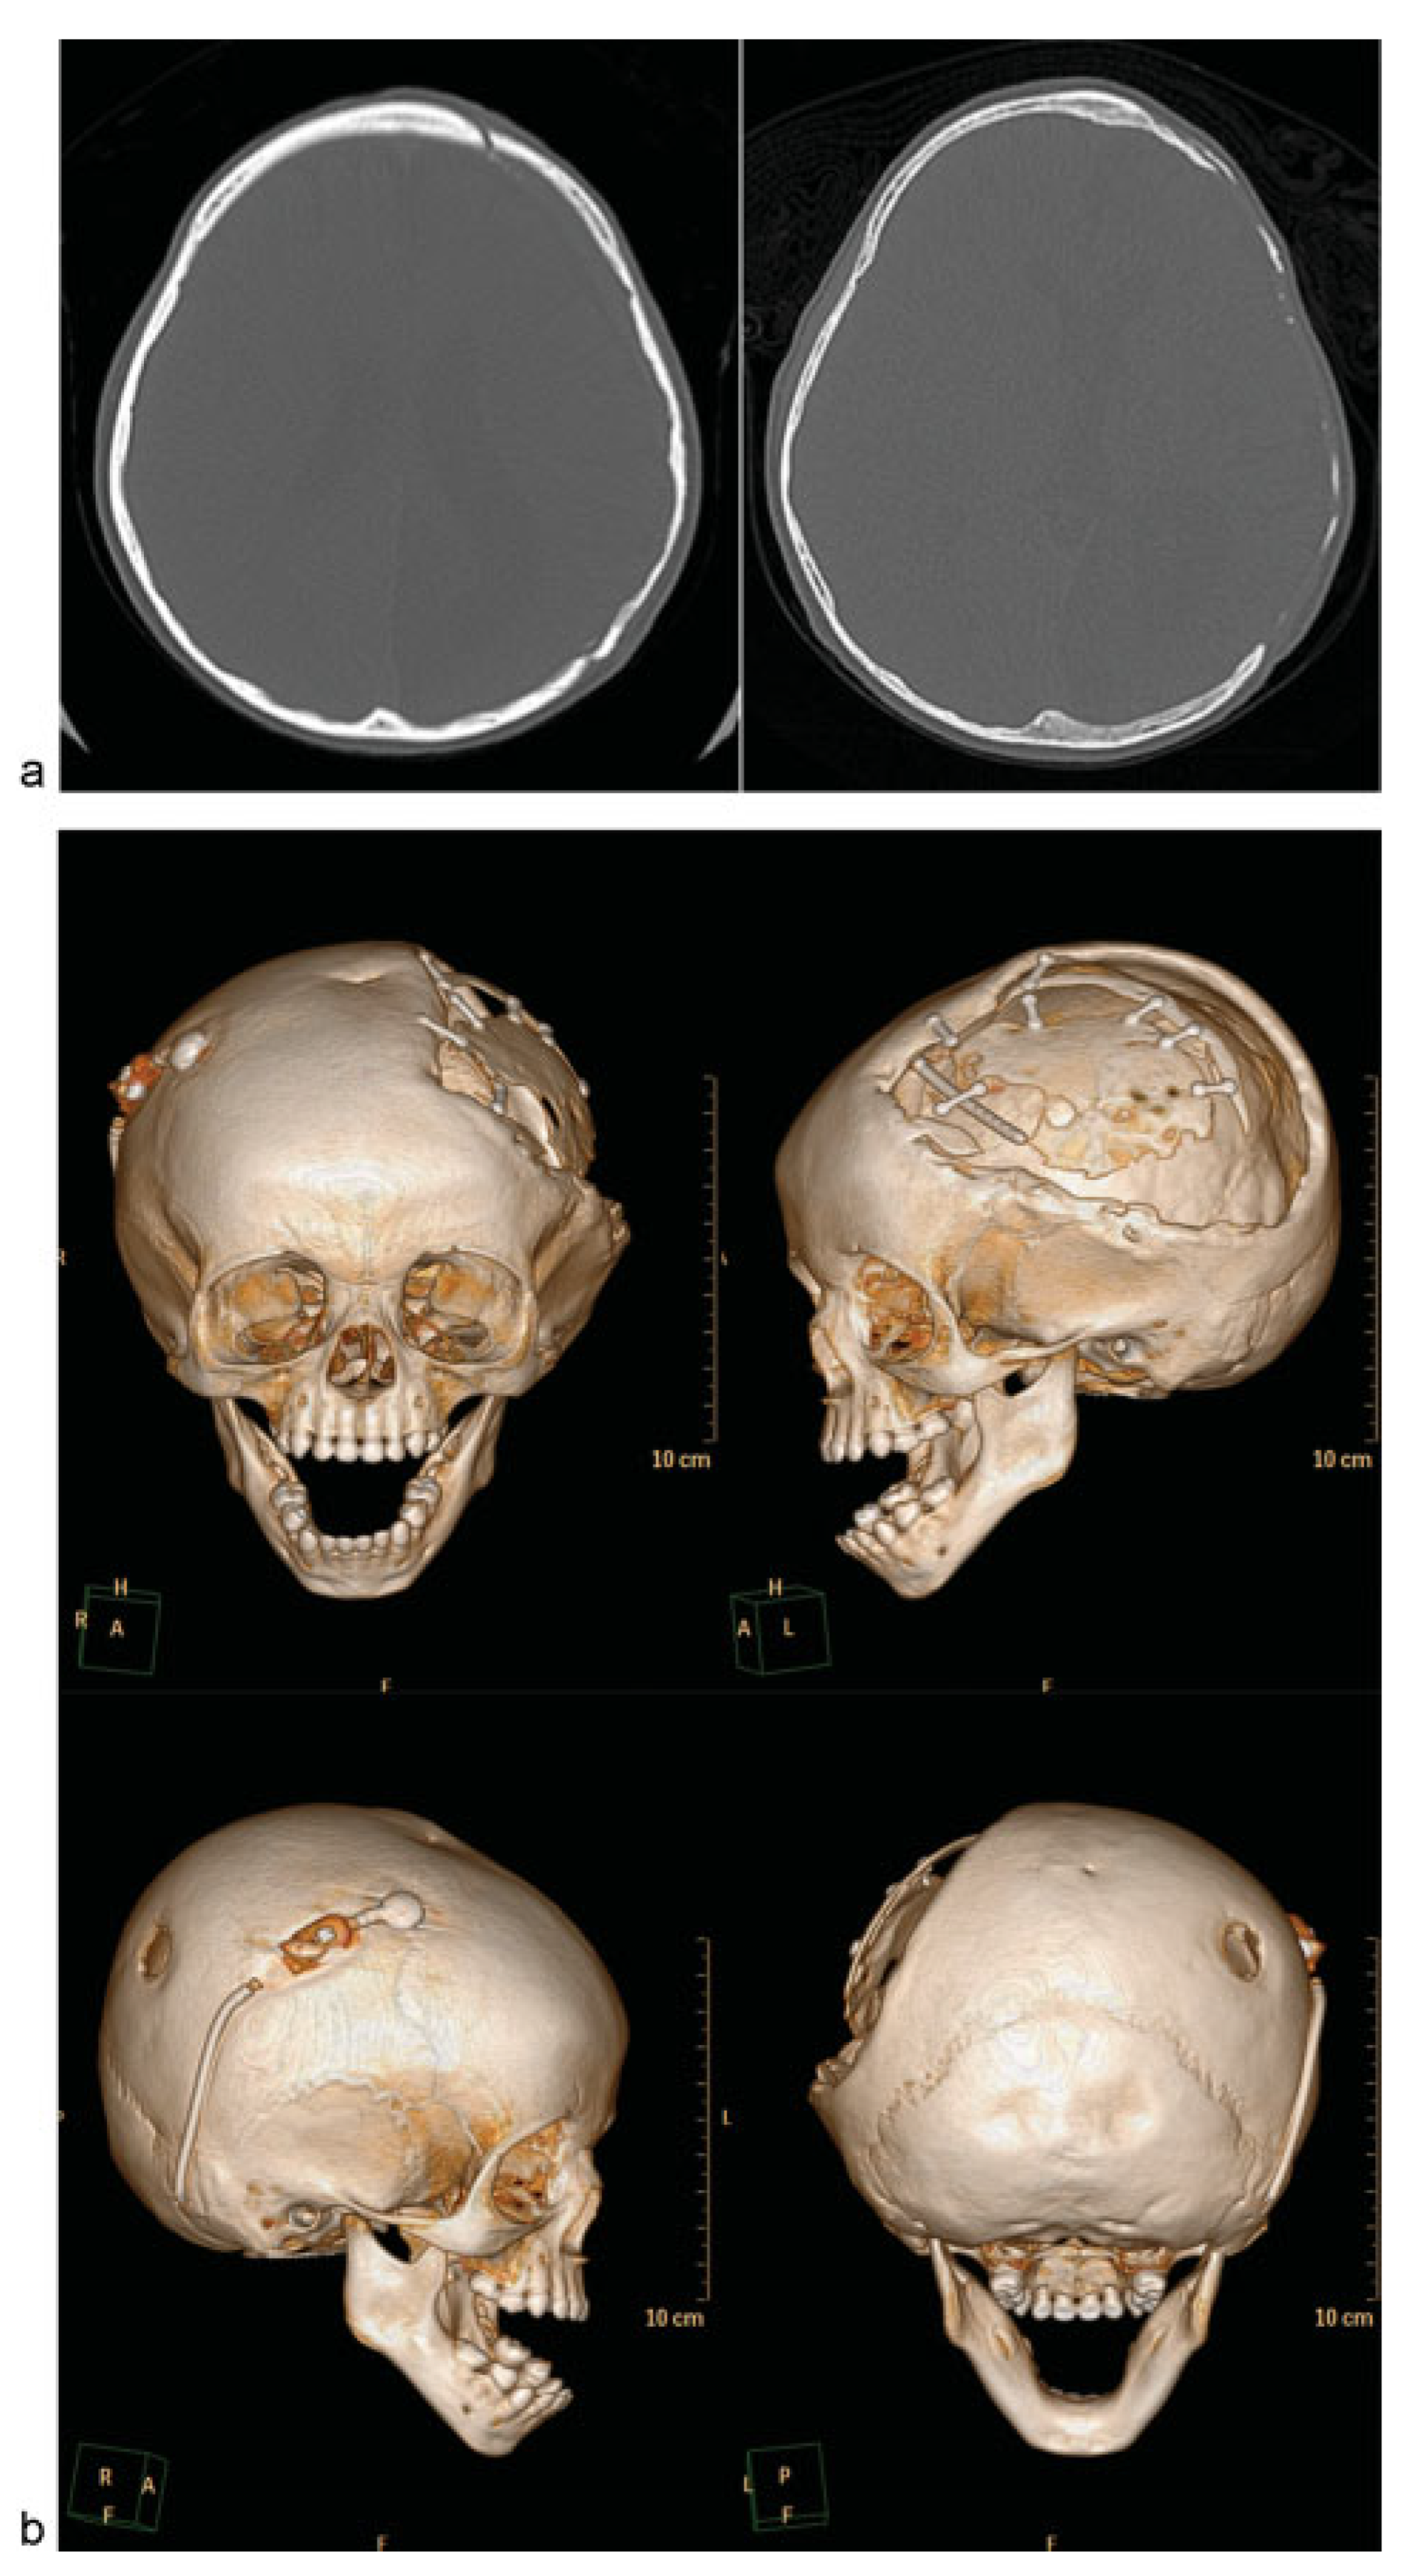

Figure 5.

Case 3: A 5-year-old girl with large left frontotemporoparietal defect after emergent decompressive craniectomy for acute subdural hematoma, subsequent loss of bone from resorption, and multiple attempts at autologous cranioplasty during her “immature” skeletal years. She eventually underwent computer-modeled alloplastic reconstruction as her definitive treatment after she turned 5 years old. (a) Frontal view and three-dimensional (3D) computed tomographic (CT) image used for planning and customized implant fabrication.(b) On-table and intraoperative views demonstrating large defect. (c) Fixation of customized porous polyethylene implant. (d) Six-month postoperative views with good contour reconstruction.